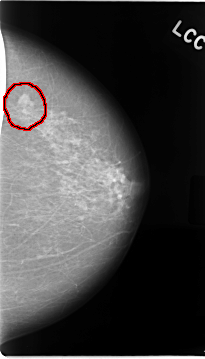

C_0018_1.LEFT_CC

FILE: C_0018_1.LEFT_CC.OVERLAY

TOTAL_ABNORMALITIES 1

ABNORMALITY 1

LESION_TYPE MASS SHAPE LOBULATED MARGINS MICROLOBULATED

ASSESSMENT 5

SUBTLETY 5

PATHOLOGY MALIGNANT

TOTAL_OUTLINES 1

BOUNDARY